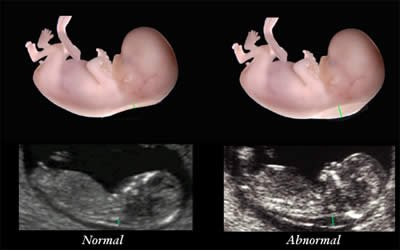

Với thai nhi có kích thước đầu mông từ 45 - 84 mm, độ mờ da gáy thường sẽ dưới 2,5mm. Những thai nhi có độ mờ da gáy nhỏ hơn 1,3 mm thì nguy cơ mắc hội chứng Down khá thấp.

Nếu độ mờ da gáy cao bất thường, bác sĩ sẽ chỉ định cho sinh thiết gai nhau hoặc chọc ối vào tuần 17-18 của thai kỳ để chẩn đoán bệnh. Lần siêu âm này cũng có thể phát hiện một số dị tật khác như thai vô sọ, khe hở thành bụng, không xương mũi...